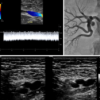

Advanced Echo Online Course features the latest education on established and emerging cardiovascular ultrasound technologies. Combining the course directorships of Echo Hawaii and State-of-the-Art Echocardiography, expert faculty discuss state-of-the-art technologies with a particular focus on how they can be effectively applied in the clinical setting. Case-based approaches are used to discuss new and established applications of echocardiography for diagnosis and guiding management in patients with a broad array of cardiovascular conditions.